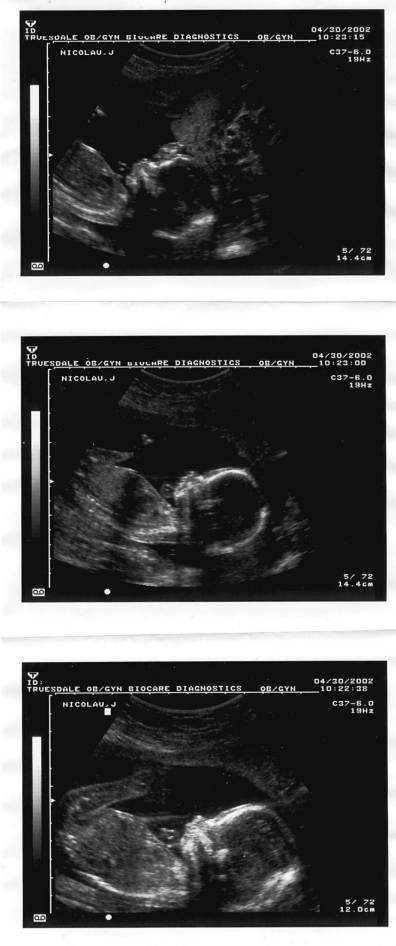

هنا جنينك في الاسبوع الثامن عشر

صورته في الاسبوع التاسع عشر